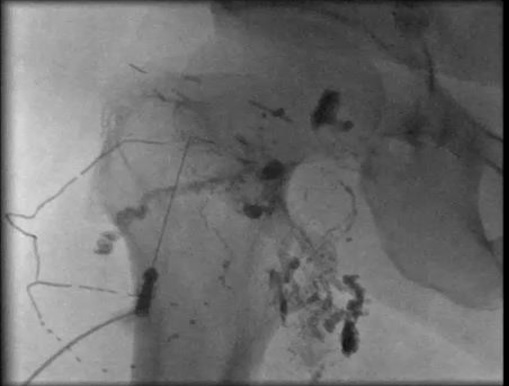

55yo 起搏器导丝滞留>1年,经血管内电极取出失败后,开胸在下腔静脉口剪断。术后出现淋巴囊肿,经皮穿刺引流240ml/8小时,持续5天。后淋巴囊肿无水酒精硬化治疗失败

经淋巴结穿刺淋巴造影

| 经皮淋巴结穿刺 | 淋巴漏进入淋巴囊肿 | 造影剂进一步扩大外溢 |

1: 4 nBCA 经淋巴结注射.,针道再次进入,证实是否还有漏

nBCA也直接注射到淋巴囊肿内

3天后漏仍然持续(>400ml/日)

漏没有减少,再次重复淋巴造影。原先周围nBCA仍然可见造影剂,

再穿刺两个淋巴结注射nBCA |

1周后漏引流减少,直到完全停止。 重复造影未见囊肿再显影。拔出导管.。3个月后影像学检查未再见囊肿.